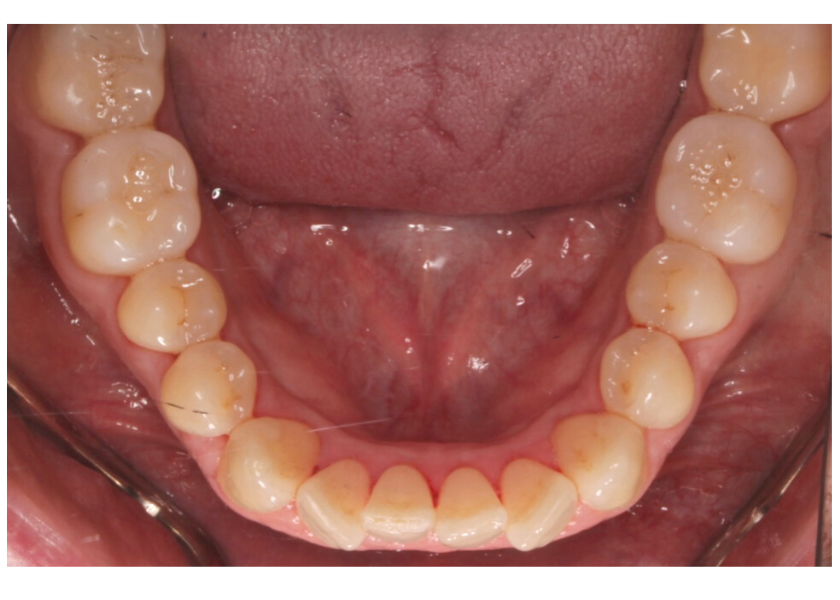

Este paciente acudió a Clínica Dental Urumea para mejorar la estética de su sonrisa. Primero se realizó un tratamiento de ortodoncia con alineadores transparentes Invisalign, para alinear y corregir la mordida cruzada.

Posteriormente, se realizaron blanqueamientos ambulatorios para mejorar

En este caso se ha optado por alineadores Vivera como método de retención.